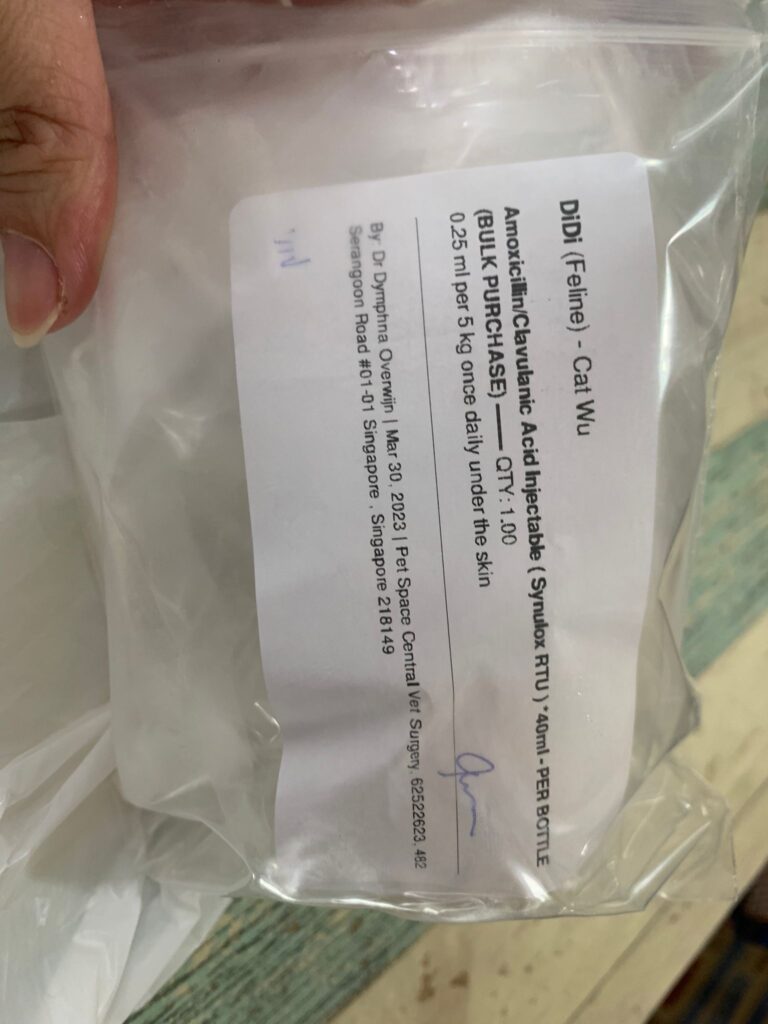

Morning; both eyes discharge look bad, clean up and put banocin on his ear. Will Subcut him and give Clav jab and bupre n put on new f patch for him

Morning: f patch intact. Apply banocin powder on ear. Still look got blood clog, didn’t bleed further. Given 5th and last Clav jab.

2pm+: checked on him, is right ear got one line, quite deep, bleeding but alr stop. Will give him 5 days ab 0.2ml clav to play safe. Given Subcut n bupre 0.2ml. 3.99kg – gain 80g in a month. Got walk about to eat

Morning: bring didi go dr nally review. 4.28kg – lose 60g in 2 days. Cbc taken. HCT up to 30.4%, EOS even higher. Reject doing liver panel. Nothing significant. Just tell me to finish up the 14 days Clav then can stop (till 2.7) Drontal n review every 2-3 months. I’ll decide again Re the allergy jabs.

HCT 29.5%, dr nally say she don’t like her EOS 3.24, but it’s a gone down figure cos March he had fenbendazole alr. Will tell them deworm him today. Alt 177 – continue ornipural. GGT 6, restart ursofalk 65mg. 15mg/kg in short. add on Clav 14 days, 0.22ml and anti histamine jabs (expire dec 23) – price $188 don’t make sense so didn’t buy.

Summary from clinic:”Didi: Restart clav inj for another 14days, and rv for rpt CBC during clav course. Conservative mgmt of hepatopathy w liver supp (O will try as cat diff to give oral meds), kiv rpt abdo US (O declined). Monitor for any jaundice/poor appetite//V+/D+. Consider maropitant nasal drops +/- nebulisation for long-term management of chronic rhinitis. *Weight loss/cachexia to be expected as suspect neoplastic process* – I didn’t reject any u/s, not true. I only show dr nally that he did u/s b4, she even comment that he got honey comb spleen ie rather sure is lymphoma le. Started didi w Clav 0.22ml and ursofalk 1.3ml today (65mg).

Subcut w B12 b com, Clav, day 03.

Clav day 06. did sneezing seem better? But I open windows now more often. Waste aircon.

Day 08 on Clav. Maybe did help in nose.

Keep sneezing. W blood also. The wall also the carrier bag also. Can’t feel anything from the teeth side, cos both blood from both nostrils. So even take head X-ray can’t see the back from the nose, just whack Clav 10 days 0.25ml. See first.

Night: given him Clav 0.25ml and ornipiral. No more oral med.

Today just courier over a bottle of Clav. Today skip medi. Tmr continue. Might miss once a week/ fortnight.

Noon: dr d “Polyclonal for didi, so no clear tumor suspect. This happens in chronic inflammation, either viral bacterial or parasitic. Or immune mediated. but very unlikely the tumor we thought…. myeloma would not look like this. so can almost 95% rule out. or try investigate lot further, maybe try to get sample from the enlarged liver or lymf nodes. lot more invasive. have you given him an antibiotic trial at some point already? dewormer?” – reminded dr d that didi alr on Clav jab 0.19ml